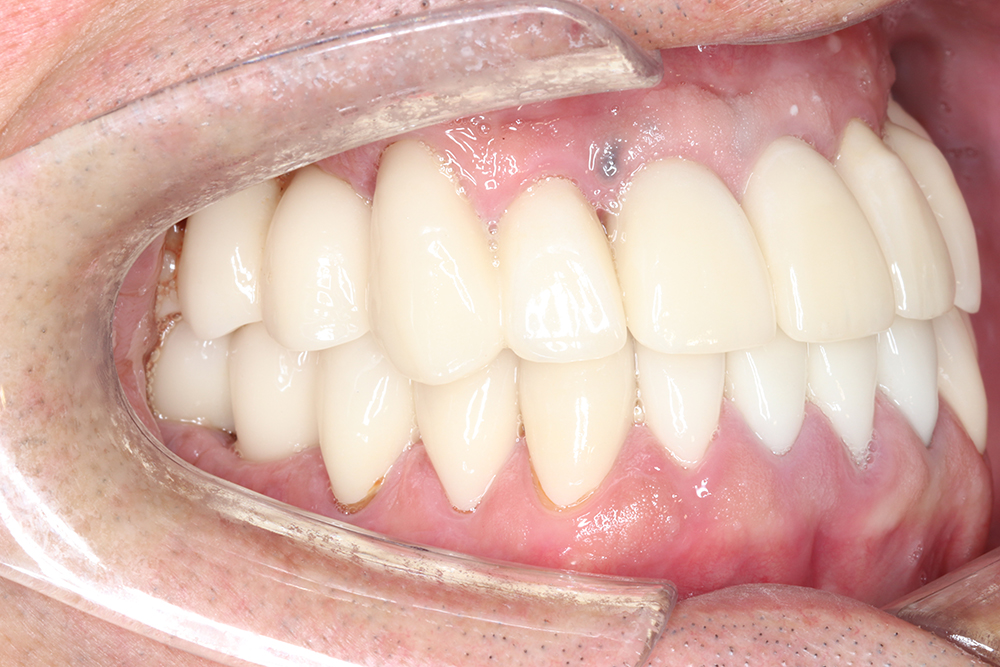

55歳 男性

- 主訴

- 前歯でしか咬めなく、食事を採るのに非常に困難で辛い

- 処置内容

- 上顎6本、下顎3本

- 治療費用

- 上顎:約230万(税込)下顎:約120万(税込)

- 治療期間

- 上顎:1年(仮歯まで8か月)下顎:8か月(仮歯まで5か月)

- リスク

- 上部構造物、仮歯の破折、術後の腫れ(3日)、人工歯根脱落リスクがあります